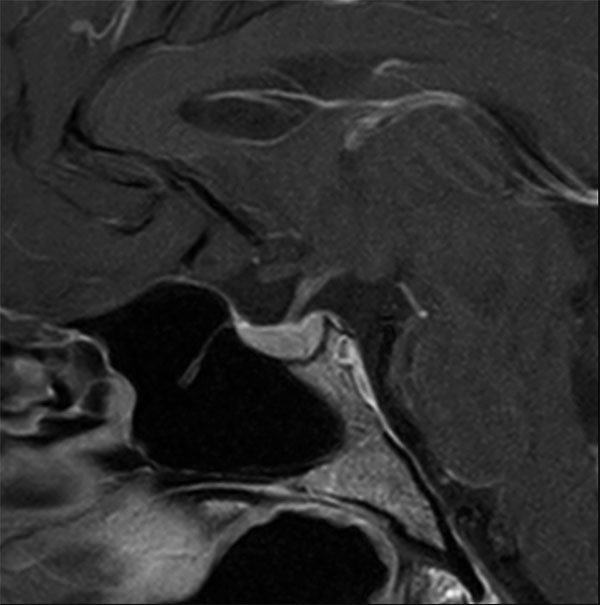

Subtle 4mm focus of decreased enhancement in the right pituitary posteriorly. No definite discrete lesion is demonstrated and the findings are equivocal for a microadenoma. Follow up imaging with MRI in six months is indicated. No suprasellar lesion or no other intracranial abnormality is demonstrated.

Sagittal T1w TSE (+gado)